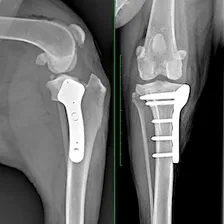

Cutting-edge surgical techniques supported by the latest evidence; TPLO for cruciate ligament tears. Management of patellar luxation, elbow, shoulder, hip & tarsal joint disease, MIPO techniques for complex fractures & limb deformities.

TPLO is considered the gold standard for managing cranial cruciate ligament tears in dogs. Yielding better outcomes with fewer complications, it is the most reliable & predictable surgery available and is recommended by most orthopaedic surgeons.